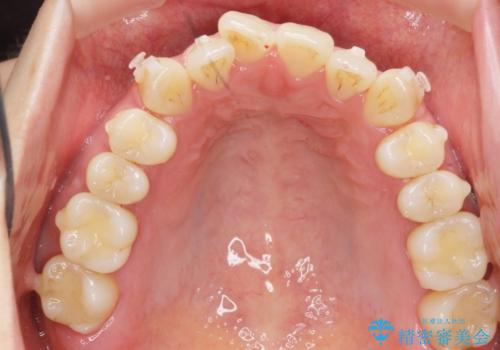

前歯のねじれを改善 マウスピース矯正インビザライン

- 目立つ前歯のねじれを改善したい、と矯正治療を希望され来院されました。

マウスピース矯正インビザラインを用いて綿密に治療計画を練り、美しい歯並びを手に入れるべく治療計画を立案します。

左側の奥歯は後方移動を行うことで、理想的な噛み合わせに整えるとともに、前歯の突出感も同時に改善することができました。